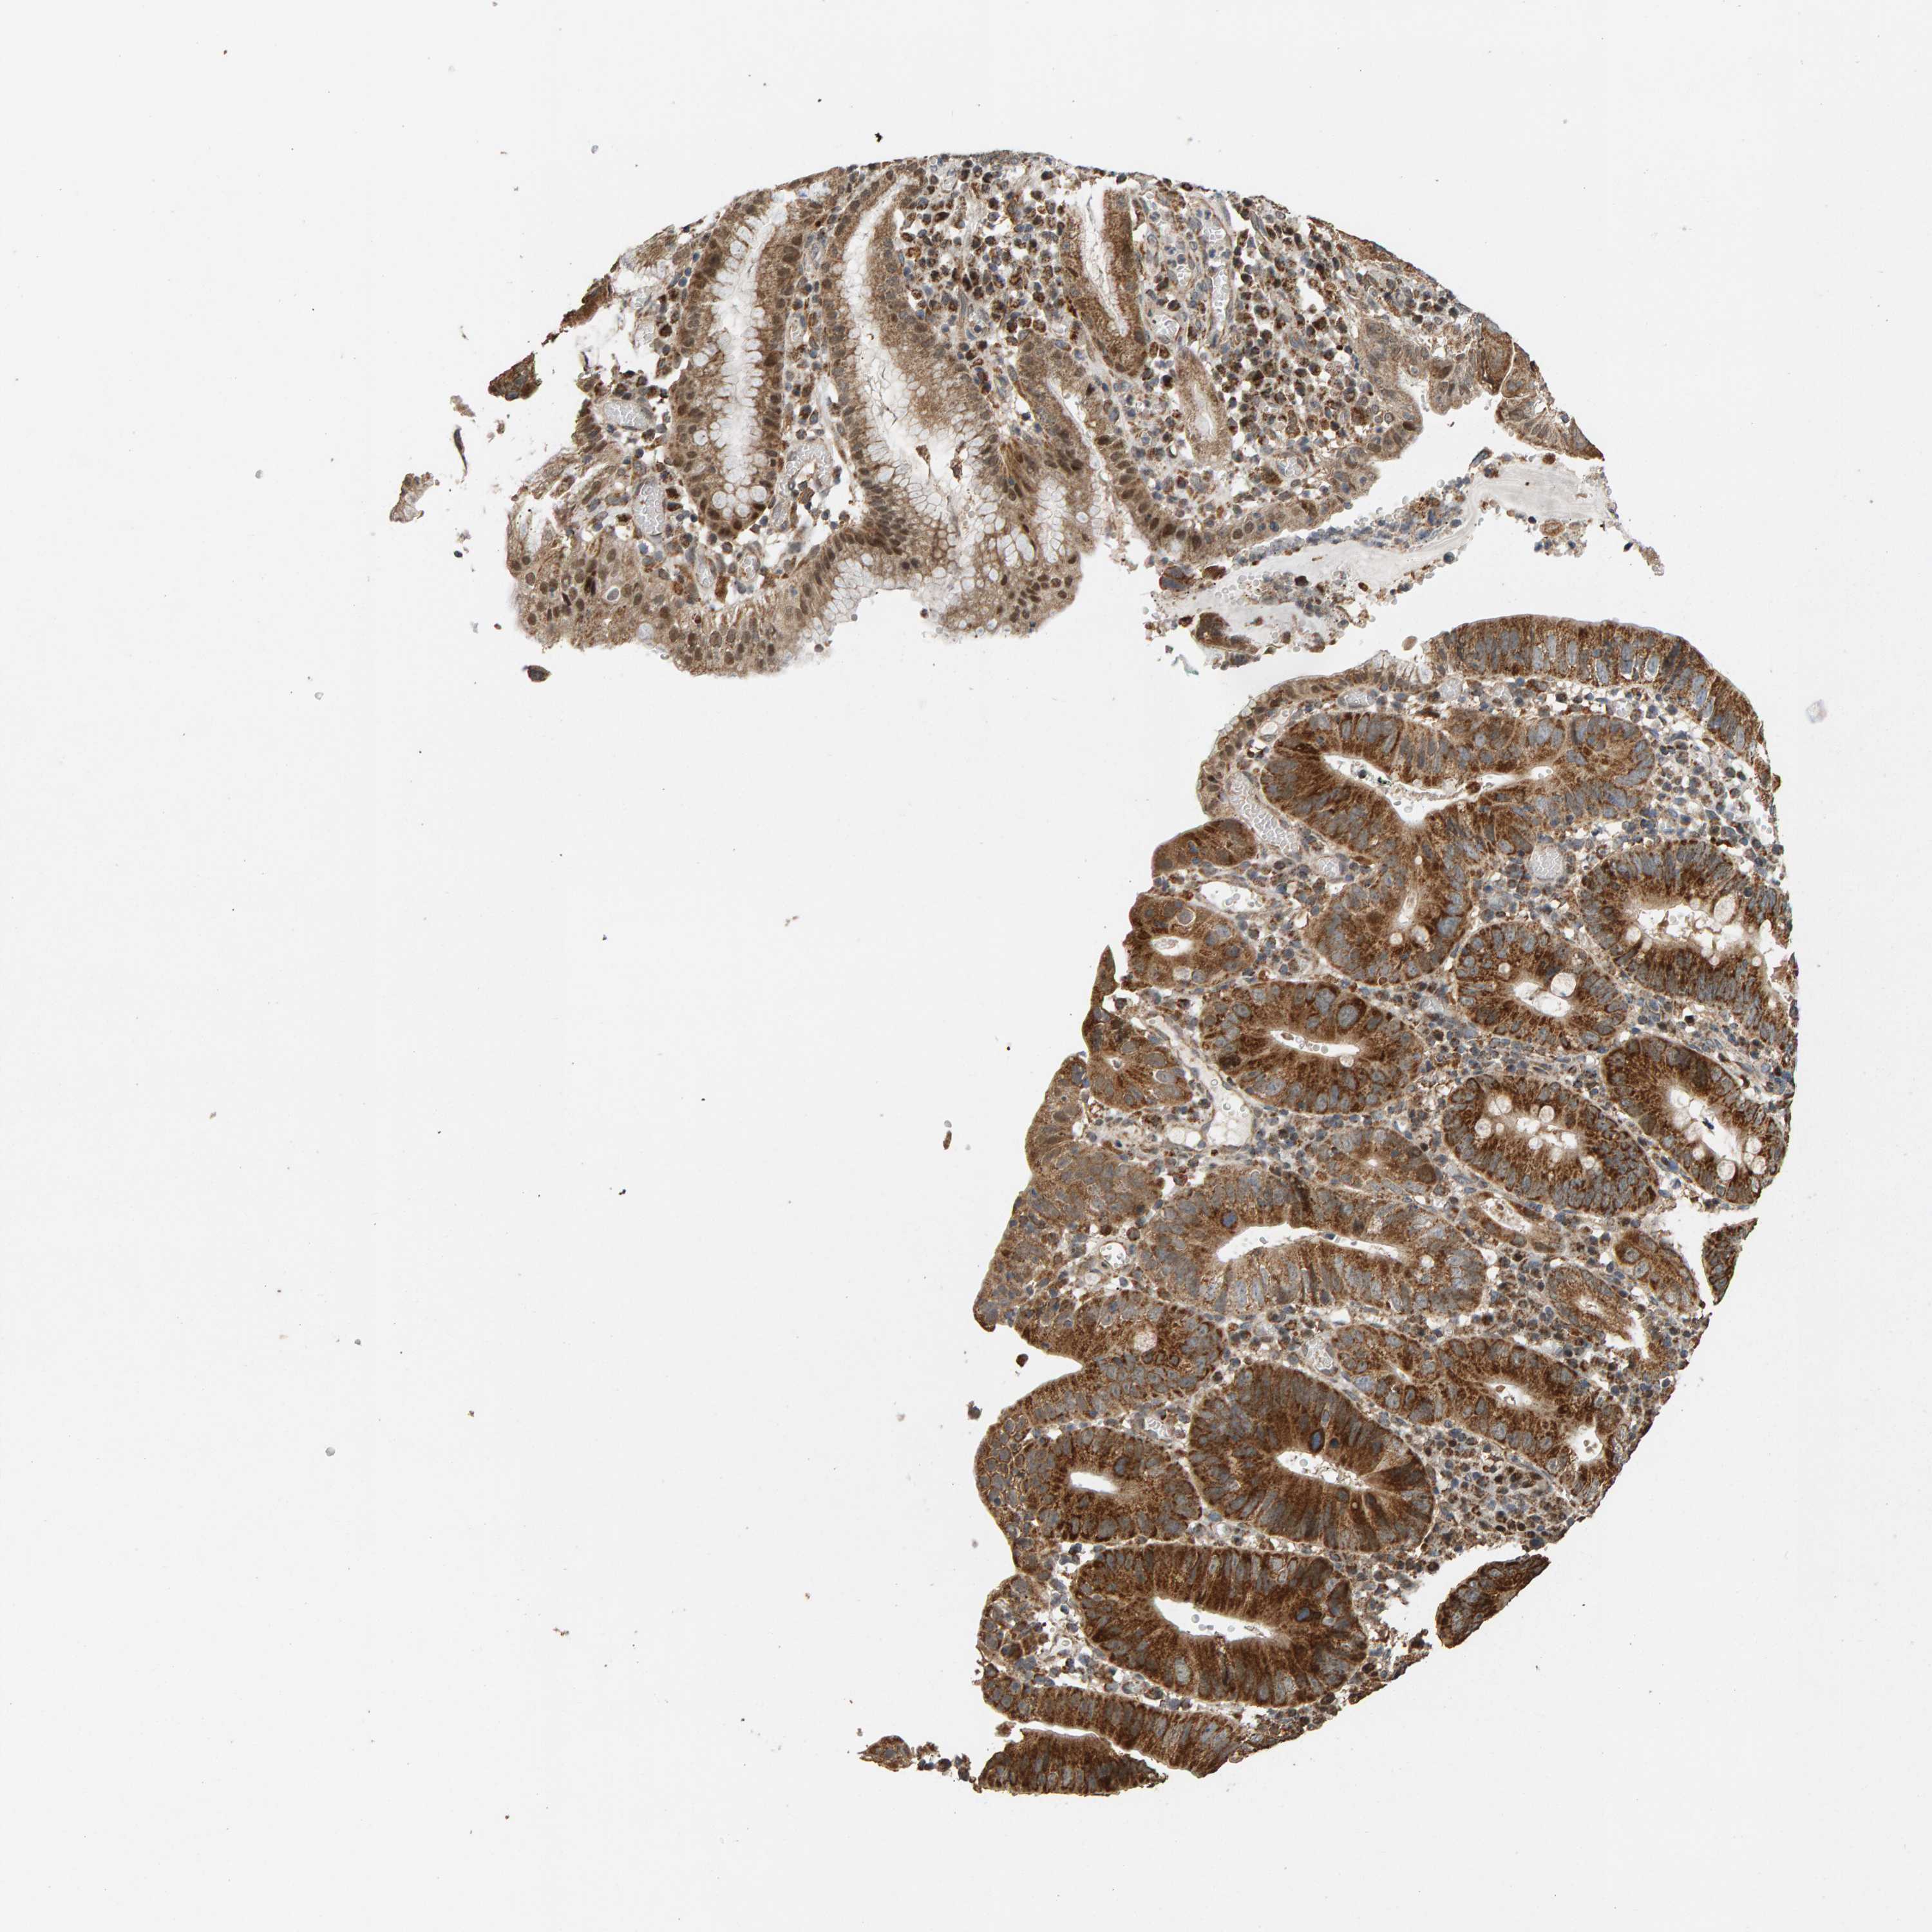

STOMACH CANCER - Protein expressioni

A mouse-over function shows sample information and annotation data. Click on an image to view it in a full screen mode. Samples can be filtered based on level of antibody staining by selecting one or several of the following categories: high, medium, low and not detected. The assay and annotation is described here.

Note that samples used for immunohistochemistry by the Human Protein Atlas do not correspond to samples in the TCGA dataset.

Antibody stainingi

Antibody staining in the annotated cell types in the current human tissue is reported as not detected, low, medium, or high, based on conventional immunohistochemistry profiling in selected tissues. This score is based on the combination of the staining intensity and fraction of stained cells.

Each image is clickable and will lead to virtual microscopy that enables deeper exploration of all samples and also displays staining intensity scores, fraction scores and subcellular localization as well as patient and tissue information for each sample.

Antibody HPA006311

Antibody HPA022904

Staining

High

Medium

Low

Not detected

Intensity

Strong

Moderate

Weak

Negative

Quantity

>75%

75%-25%

<25%

None

Location

Nuclear

Cytoplasmic/membranous

Cytoplasmic/membranous,nuclear

Adenocarcinoma, NOS

Adenocarcinoma, High grade